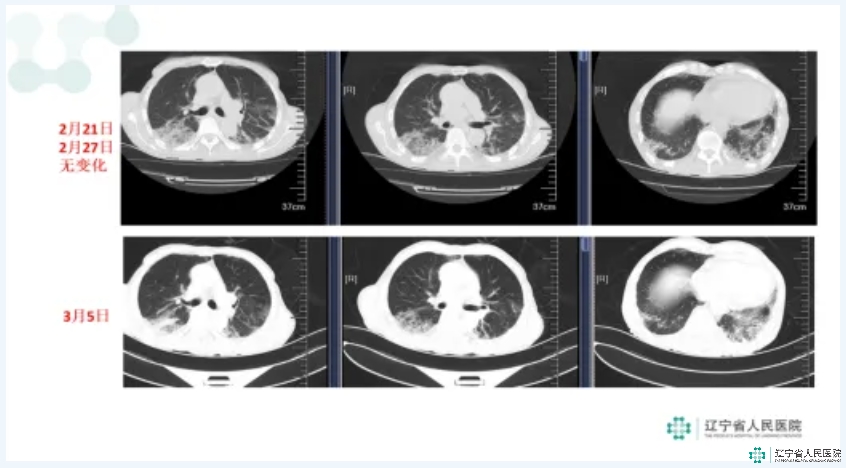

入院时,未吸氧状态下周身皮肤及口唇舌质紫绀明显,3升/分吸氧状态下血氧饱和度仅波动于93-95%。呼吸频率明显加快,30-35次/分。听诊双肺呼吸音减弱,背部可闻及明显帛裂音,左下肺明显。完善肺CT可见双肺广泛间质改变,对比前两次肺CT明显进展加重。初步诊断为间质性肺疾病。

虽然病情隐匿复杂,但经过科室多位专家多角度分析明确诊断后,迅速给予针对性、个性化的综合治疗,患者病情出现明显好转,静息状态下气短明显缓解,但活动后仍有喘息,静息位呼吸频率改善,20次/分左右,指脉氧饱和度较前上升, 静息状态1-2升/分吸氧状态下血氧饱和度维持于95-98%之间,四肢关节红肿及皮疹溃疡等有所减轻,肺部帛裂音减少,肺部CT影像学明显改善。

相关体征、指标及影像图片对比: